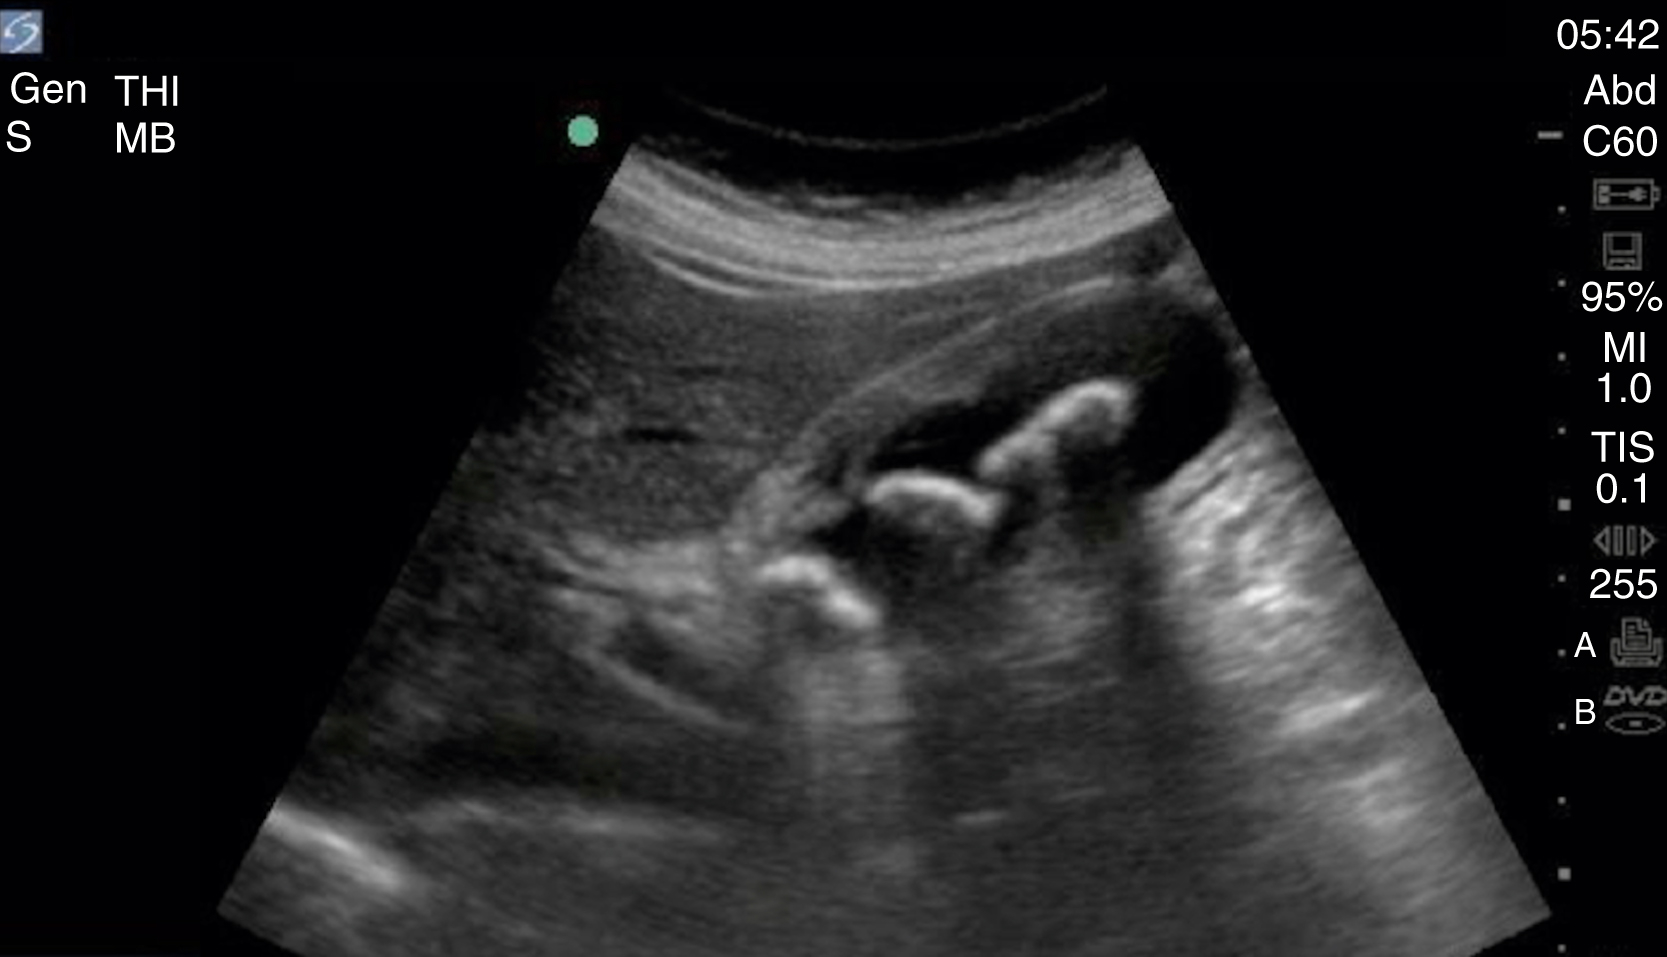

The FAST examination technique uses a low-frequency broadband transducer (2–6 MHz) to evaluate dependent peritoneal spaces, pleural spaces, and the pericardium for free fluid, which in the trauma patient is presumed to be blood. There are four main components of the basic FAST examination: (1) the right upper quadrant (RUQ) view, (2) the left upper quadrant (LUQ) view, (3) the pelvic view and (4) the cardiac view ( Fig. e3.1 ). The E-FAST includes anterior chest views to evaluate for pneumothorax. The RUQ view evaluates for fluid in the thorax (above the diaphragm) ( Video e3.1 ), hepatorenal space (Morison pouch) and the paracolic gutter (inferior edge of the liver and right kidney) ( Video e3.2 ), moving cephalad to caudad. The LUQ view, found slightly more superior and posterior than the RUQ, should mimic the RUQ views, but also include the subdiaphragmatic space, because free intraperitoneal fluid tends to accumulate here initially. The pelvis should be evaluated in the transverse and longitudinal planes, where fluid may be detected deep to the uterus (in females) or in the retrovesical space (in males) ( Video e3.3 ). The cardiac evaluation can be performed in either the subcostal (or subxiphoid) or parasternal window ( Video e3.4 ). Evaluation for pneumothorax uses a low or high-frequency transducer at a shallow depth, placed along the anterior chest wall and will be discussed in more detail in subsequent sections.

Negative FAST images. (A) Subxiphoid view with no pericardial effusion. (B) Negative RUQ view showing the thorax and hepatorenal space without the paracolic gutter visualized. There is mirroring and loss of the spine, indicating a negative thorax. (C) Negative paracolic gutter area by the liver tip in the RUQ view. (D) LUQ view showing negative thorax, as in B, and splenorenal space. (E) Negative transverse bladder view. (F) Negative sagittal bladder view.